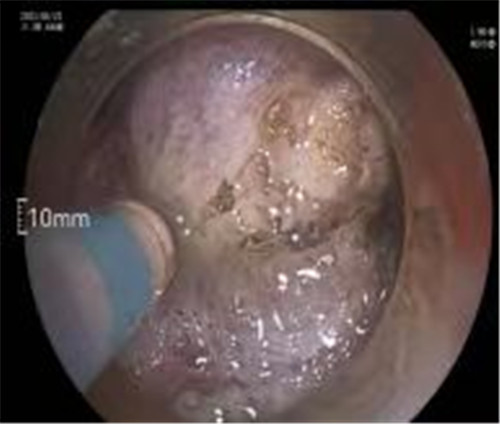

近期病例之一,圖片依次為:胃鏡、超聲胃鏡、ESE術(shù)中、術(shù)后、切下病變。

通過內(nèi)鏡切開瘤體表面粘膜,分離后挖除瘤體,或以消化道全層切除的方法切除瘤體,并在內(nèi)鏡下縫合切口。與傳統(tǒng)手術(shù)相比,該項技術(shù)利用了人體自然通道,不會破壞人體結(jié)構(gòu),更加微創(chuàng)。不超過3cm向消化道腔內(nèi)生長為主的良性或低度惡性粘膜下腫瘤(如間質(zhì)瘤、類癌、平滑肌瘤等),都可采用ESE治療。